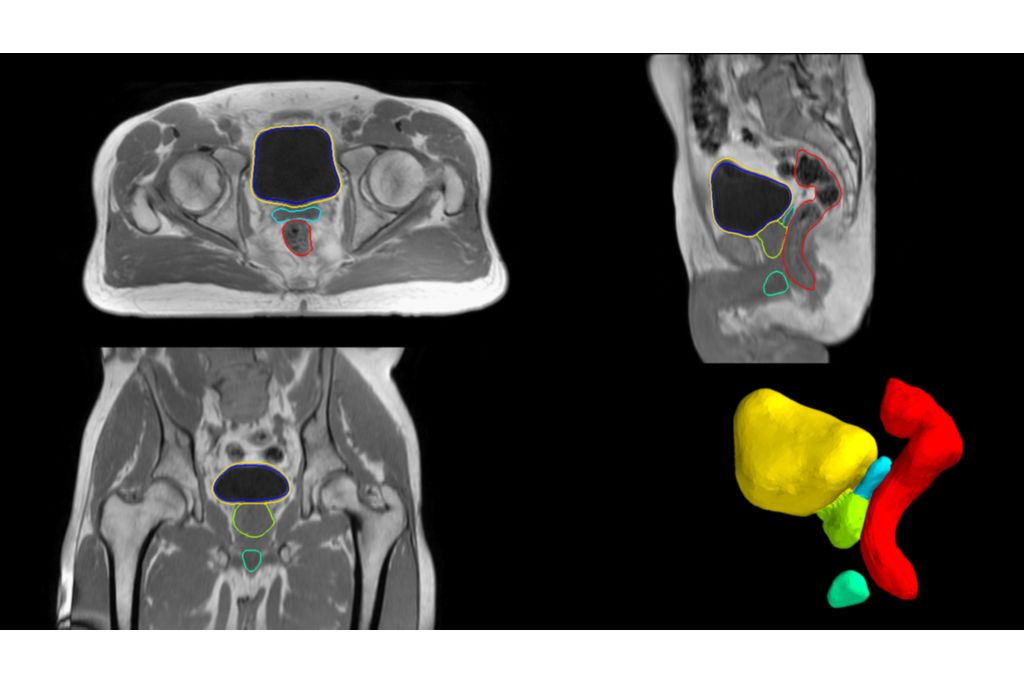

***Accurate means 95th percentile modified Hausdorff distance <5mm compared to contours made by experts manually. Average distance is <1.5 mm and is measured as average modified Hausdorff distance compared to contours made by experts manually.

**** Based on 49 cases (each for anatomical prostate, bladder, rectum, penile bulb and femur heads)